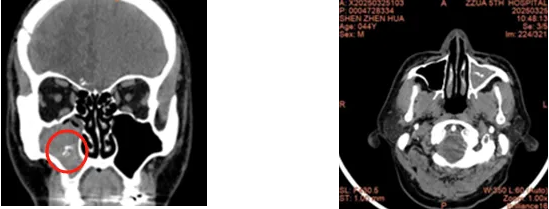

2.影像“透视眼”:鼻窦CT可以简单方便明确病变范围

▲圈中所指为真菌块在CT中的表现